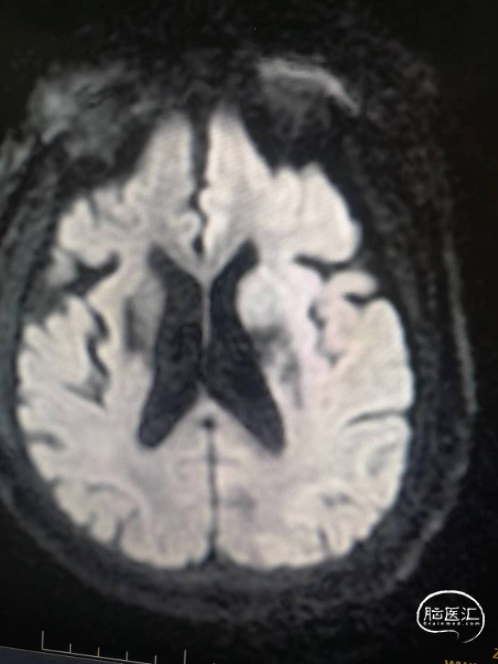

术前影像信息

符合脑内多发缺血变性灶、梗死灶(左侧大脑半球大面积急性梗死)、软化灶T2-FLAIR/DWI表现;

符合颅脑动脉硬化并多发狭窄MRA表现,左侧颈内动脉颅内段、大脑中动脉及分支未见显示,考虑闭塞或重度狭窄,建议CTA进一步检查。